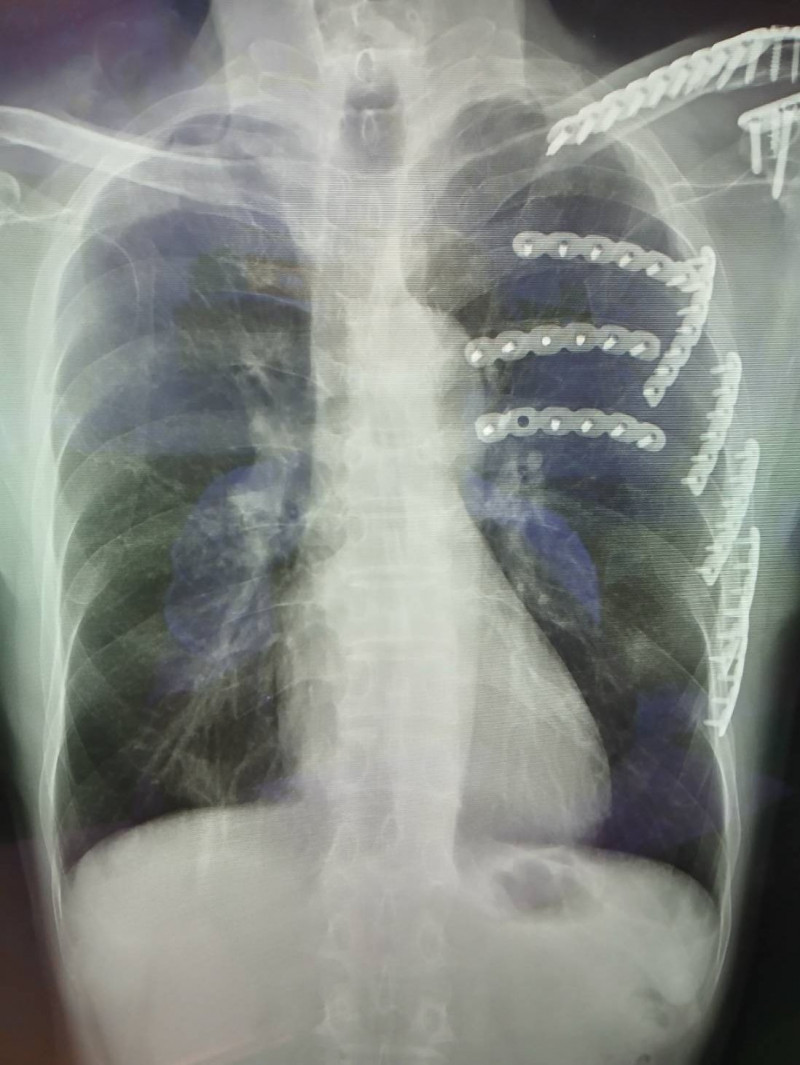

國軍台中總醫院胸腔外科主任謝志明指出,患者送醫時左側第3至7肋骨骨折合併血胸,呼吸極度困難,疼痛指數高達8分。傳統肋骨骨折多採不開刀保守治療,患者需忍受長達2至3個月的劇痛,若錯位嚴重甚至需半年才能癒合,且易引發肺炎、氣血胸等併發症。

經評估後,決定採用「胸腔鏡輔助肋骨骨折復位矯正鋼板內固定手術」,術後患者的疼痛指數迅速降至3分,呼吸困難明顯改善,也能順利咳痰與進行肺部復健,住院兩週即順利出院。